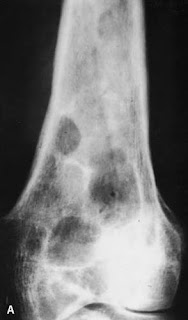

A 40 year old male, cattle farmer, presenting with pain in leg over 1 year. No history of significant trauma, infection or any other swelling in the body. Can u identify the pathology?

Radiograph

- may show expansile lytic lesion in the involved bone which can be unilocular or multilocular with coarse trabeculae

- thinning of cortex

- adjacent soft tissue swelling may be seen due to direct extension from the bone or co-existing multiple soft tissue lesions